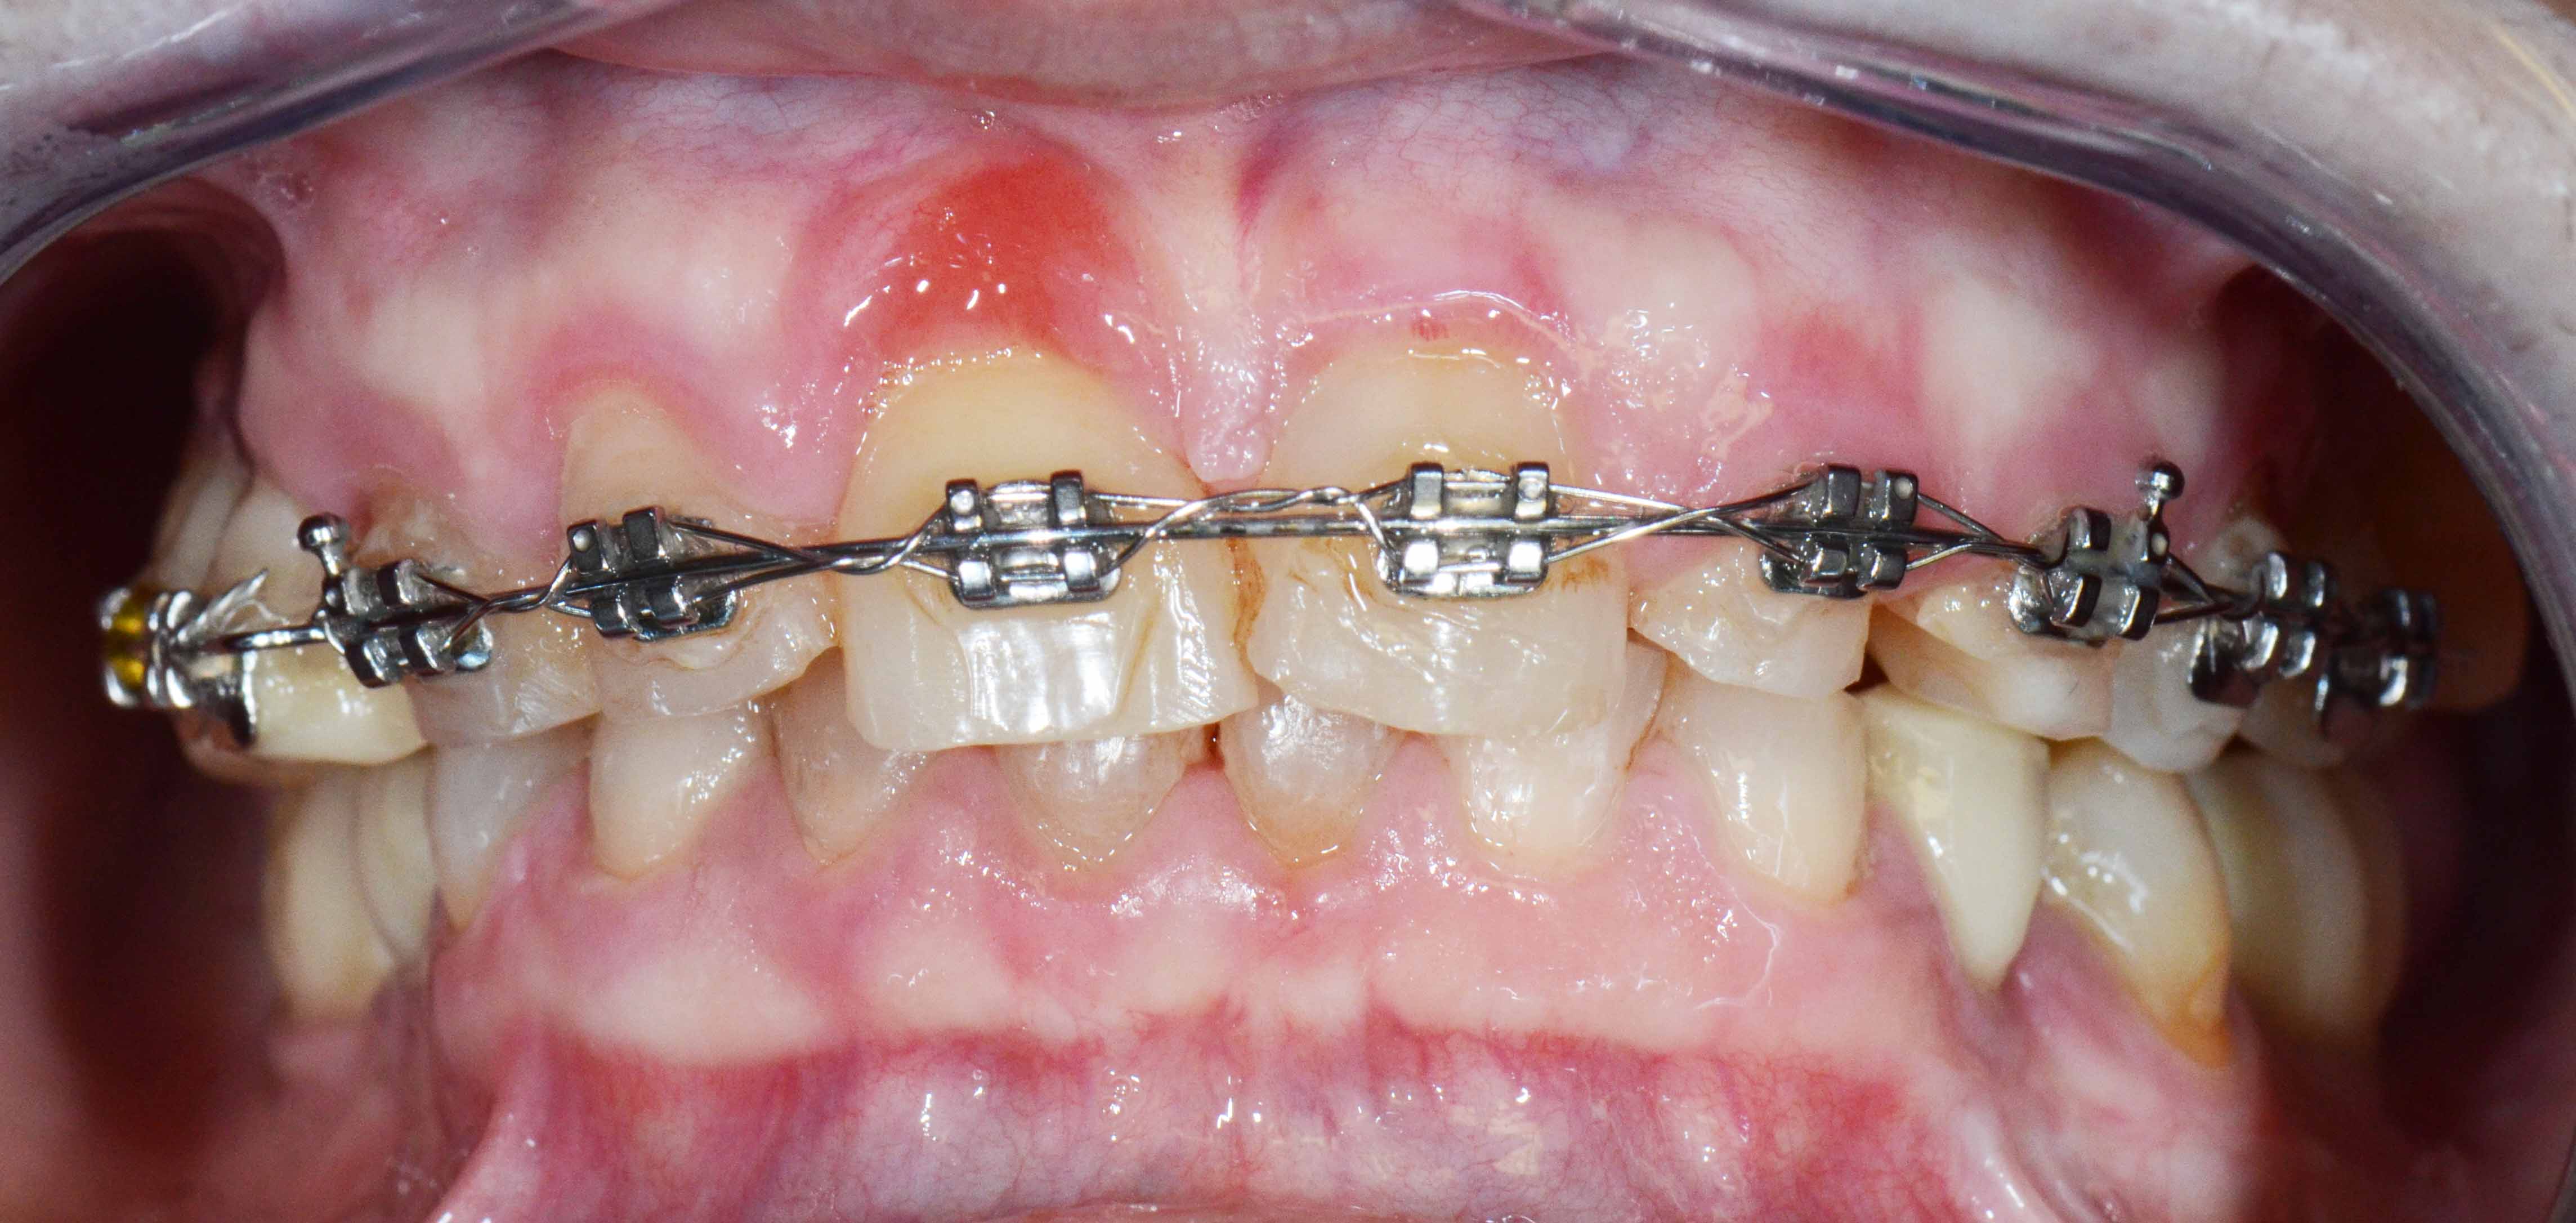

Patient with limited functions and serious aesthetics problems.

Complex Rehabilitation – The Treatment:

The natural teeth that had a good prognosis were kept and the ones that needed their position changed were moved by a fixed orthodontic brace.

Afterward a surgery was made to place some implants. The treatment was finalized by placing the ceramic crowns over the implants and teeth.